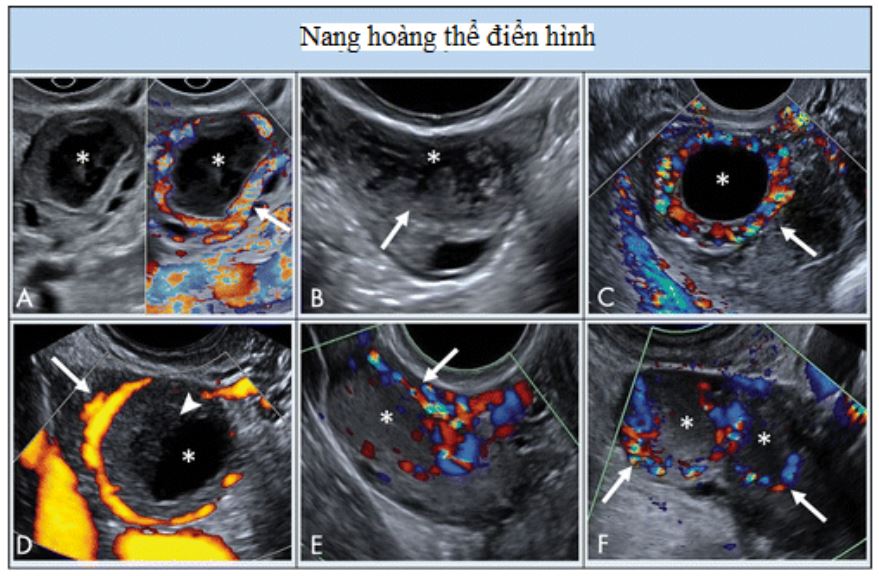

Hình 7: Hình ảnh cho thấy nang hoàng thể điển hình. A, hoàng thể có siêu âm Doppler màu và không Doppler cho thấy thành phần nang trung tâm (dấu sao) với thành dày trơn láng, vô mạch bên trong, và mạch máu ở ngoại vi (mũi tên). B, nang hoàng thể có thành phần trung tâm, thành dày, và bờ răng cưa bên trong (mũi tên). C, Nang thành dày trống âm (dấu sao) với nhiều mạch máu ngoại vi (mũi tên). D, Doppler năng lượng cho thấy mạch máu ngoại vi (mũi tên) trong nang này (dấu sao) với cục máu đông (đầu mũi tên). E, Nang hoàng thể với vùng phản âm kém (dấu sao) mà không có thành phần nang trung tâm nhưng có mạch máu ngoại vi (mũi tên). F, Hai nang hoàng thể bởi hai vùng phản âm kém (dấu sao) với mạch máu ngoại vi (mũi tên).